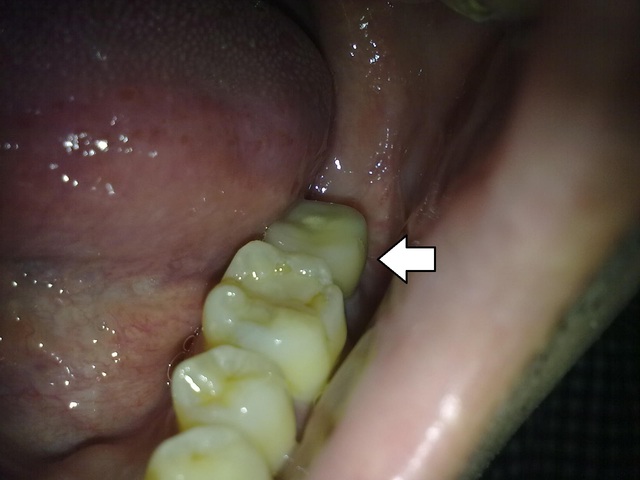

前天於把牙植好了~~